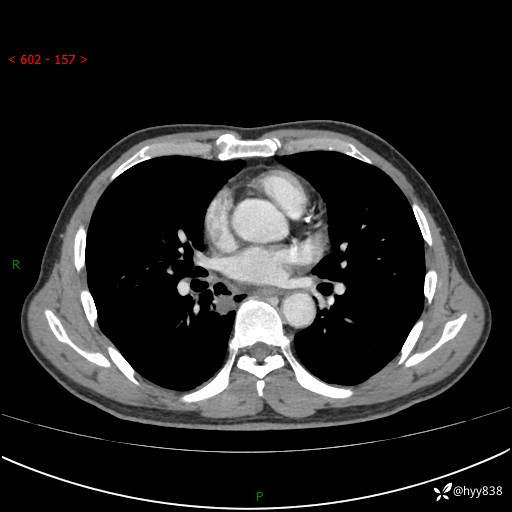

69岁/男,发现肺部病变6天。该有的征象都有,肉芽肿 VS 肿瘤,一念之间---(有结果)

主诉:发现肺部病变6天。

现病史:患者6天前于我院泌尿外科住院,住院期间行胸部CT检查,提示“肺部病变”,患者无畏寒、发热、盗汗、咳嗽、咳痰、咯血、胸痛、呼吸困难,无反酸、腹痛、腹泻、头痛、头晕等不适。未予特殊处理,现为进一步诊治,门诊以“肺肿物”收入我科。 患者本次起病以来,精神食欲尚可,大小便正常,体力及体重无明显变化。

胸部CT平扫+增强